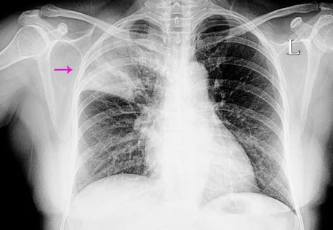

4. 폐렴, 어떻게 진단하나요? 병력 청취부터 영상 검사까지

폐렴 진단은 환자의 병력 청취, 신체 검사, 혈액 검사, 가래 검사, 흉부 X-ray, CT 등 다양한 검사를 통해 이루어집니다.

- 흉부 X-ray: 폐렴 병변 위치와 크기를 확인합니다.

- CT: 흉부 X-ray보다 더 정밀하게 폐렴 병변을 확인할 수 있습니다.